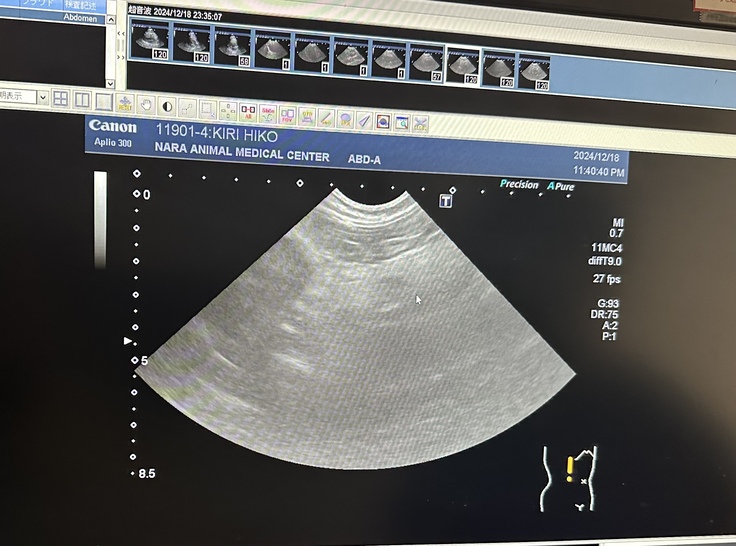

緊急を要すると思い『奈良動物医療センター』に受診しました。

採血とエコー検査の結果『急性膵炎』と診断され、入院になりました。

5日前から膵炎発症し、相当お腹が痛かったでしょうと。詳しい採血結果を待たないと確定診断できないそうですが、膵臓の周囲が肥厚しているので膵炎に間違いないということで治療開始して頂きました。